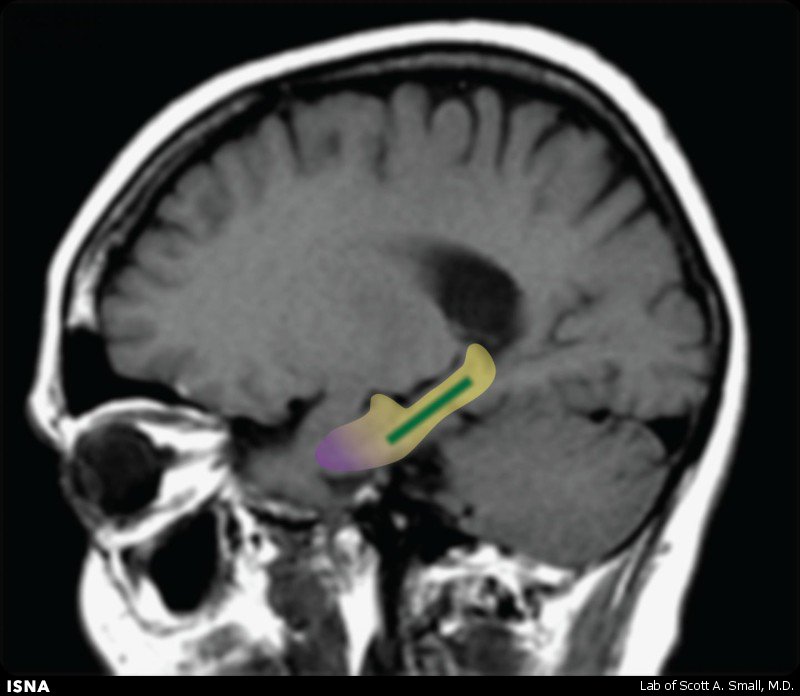

آزمایش‌های جدید دانشمندان مرکز پزشکی دانشگاه کلمبیا نشان داد فلاونون، زوال حافظه مرتبط با سن را در بزرگسالان مسن سالم معکوس می‌کند. به گزارش جی پلاس، با بالارفتن سن، بسیاری از اشخاص نوعی زوال را در توانایی‌های شناختی‌شان شامل یادگیری و به یادآوردن اسامی آشناهای جدید و ... تجربه می‌کنند. این زوال حافظه مرتبط با سن عادی، اوایل بزرگسالی آغاز می‌شود اما معمولا اثر قابل‌توجهی بر روی کیفیت زندگی افراد ندارد تا این که آن‌ها به دهه‌های پنجاه و شصت سالگی عمرشان می‌رسند. زوال حافظه مرتبط با سن، متفاوت از نارسایی حافظه‌ مخربی است که در افراد مبتلا به آلزایمر رخ می‌دهد که در آن، فرآیند زوال، عصب‌ها را در بخش‌های مختلف مغز شامل مدارهای حافظه تخریب می‌کند. مطالعات پیشین نشان داده بودند بروز تغییرات در بخش خاصی از مغز به نام dentate gyrus با زوال حافظه مرتبط با سن ارتباط دارند؛ اما تاکنون، آزمایشات بر روی انسان‌ها فقط عامل ارتباطی و نه سببی این بخش از مغز را نشان داده بودند. به منظور بررسی این موضوع که آیا dentate gyrus منبع زوال حافظه مرتبط با سن در انسان‌هاست یا خیر، محققان بررسی کردند که آیا ترکیبی موسوم به فلاونول کاکائو می‌تواند عملکرد این ناحیه از مغز و در نتیجه حافظه را ارتقا بخشد یا خیر. فلاونول مشتق‌شده از دانه‌های کاکائو پیش‌تر ارتباطات عصبی را در dentate gyrus موش‌ها نشان داده بود، این در حالی است که اکثر شیوه‌های پردازش کاکائو بخش عمده فلاونول موجود در گیاه خام آن را حذف می‌کند. در این پژوهش، ۳۷ داوطلب سالم بین سنین ۵۰ تا ۶۹ سال به طور تصادفی رژیم غنی از فلاونون (۹۰۰ میلی گرم فلاونون در روز) یا رژیم با فلاونون پایین (۱۰ میلی‌گرم فلاونون در روز) را به مدت سه ماه تجربه کردند. دانشمندان تصویربرداری از مغز و آزمایش‌های حافظه را پیش و پس از پژوهش بر روی هر شرکت‌کننده انجام دادند. تصویربرداری به کار رفته حجم خون موجود در dentate gyrus را اندازه‌گیری کرد و آزمایش حافظه نیز شامل تمرین الگوی شناختی ۲۰ دقیقه‌ای بود که برای ارزیابی نوع حافظه‌کنترل‌شده توسط dentate gyrus طراحی شده بود. دانشمندان با بررسی تصاویر مغز متوجه پیشرفت قابل‌توجه در عملکرد این بخش از مغز در افرادی شدند که نوشیدنی کاکائوی غنی از فلاونون مصرف کرده بودند. این گروه همچنین در آزمایشات حافظه عملکرد بسیار بهتری داشتند. دانشمندان یادآوری کرده‌اند که یافته‌های این پژوهش باید در مطالعات گسترده‌تری تایید شوند. فلاونون همچنین در برگ چای و میوه‌ها و سبزیجات خاصی یافت می‌شود اما میزان کلی و همچنین اشکال و ترکیبات خاص آن بسیار متغیر است. جزئیات این مطالعه در نشریه Nature Neuroscience منتشر شد. منبع: خبرگزاری ایسنا